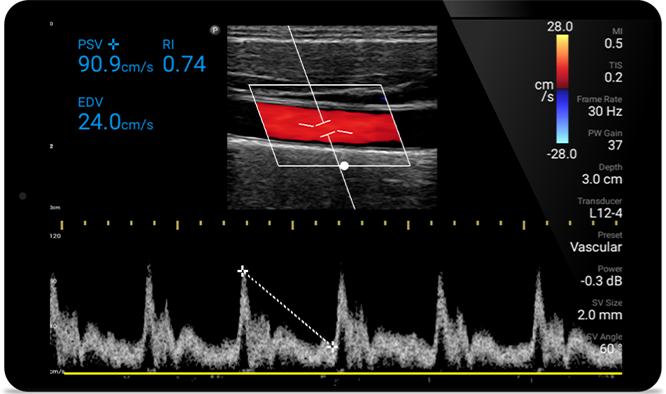

From revealing the subtle details of an image to uncovering enriched tissue definition from multiple angles, Lumify can help you make real-time decisions with more confidence from assessment through recovery.